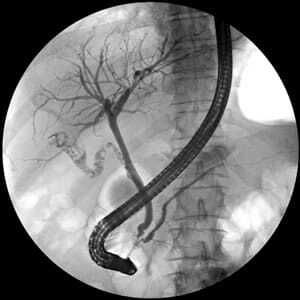

This surgical series is aimed at clinical year medical students and junior doctors. The objectives of this second session are to provide a comprehensive understanding of biliary sepsis, including relevant anatomy and pathological cause. By the end of the teaching, you should be able to recognise, diagnose, and manage this condition effectively in an acute hospital setting.

Join our 6pm Surgical Series on Biliary Sepsis, an essential learning for clinical year medical students and junior doctors. Enhance your understanding of its associated anatomy and pathological cause. Gain the necessary expertise in recognizing, diagnosing, and effectively managing Biliary Sepsis within an acute hospital environment. This comprehensive session is not to be missed.

3. Diagnosis of Biliary Sepsis: The participants should be able to recognise the clinical signs and symptoms of biliary sepsis and interpret relevant laboratory and imaging investigations to formulate a confirmed diagnosis.